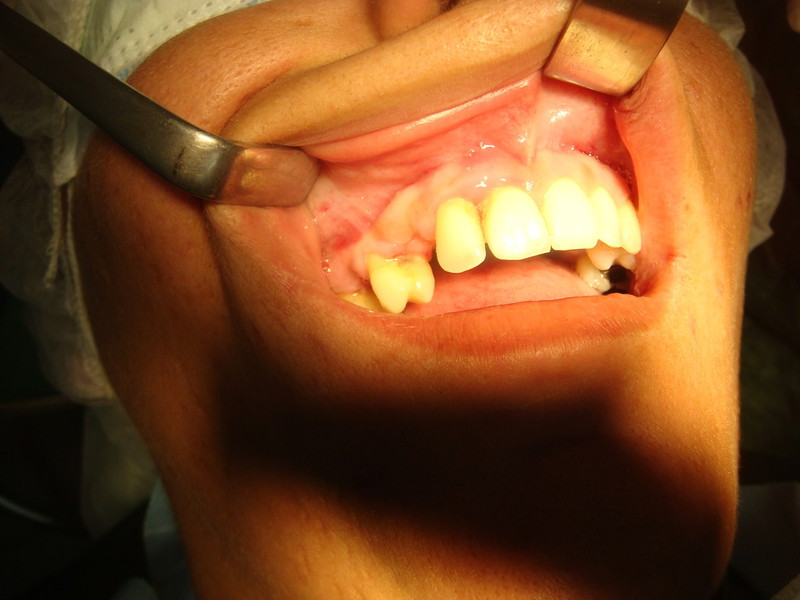

Rigenerazione Gravi difetti parodontali

rigenerazione grave difetto parodontale a carico del 46